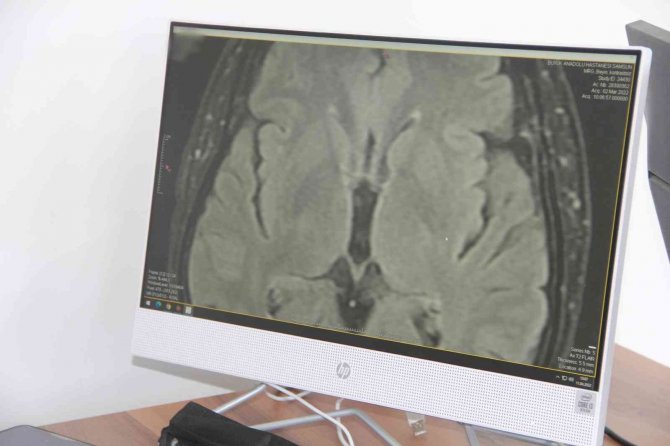

Beyin Cerrahisi ’Parkinson’a Tedavi İmkanı Sunuyor

Parkinson hastalığının nöroloji servislerince tanı ve takibinin yapıldığı ve medikal tedavisinin düzenlendiğini söyleyen Opr. Dr. Karkucak, hastalığın ilerlemesi veya ilaçların yeterli gelmemesi durumlarında uygun hastalarda beyin cerrahisine başvurulabildiğini ifade etti.

Son yıllarda aktif olarak kullanılan cerrahi tedaviden bahseden Karkucak, "Beyin cerrahisinin son yıllarda parkinson hastalığında devreye girmesi sonucu, özellikle derin beyin stimülasyonu işlemi hareket bozukluğu merkezlerinde ve nöromodulasyon merkezlerinde planlanıp uygun hastada, uygun cerrahi tedavi protokolleriyle uygulanmaktadır ve artık hareket bozukluğu, titreme, yavaş yürüme, yürüyememe gibi şikayetler çok ciddi derecede gerilemektedir. Parkinson kader değil tedavi edilebilir bir hastalıktır" dedi.

Parkinson hastalığındaki risk gruplarından da söz eden Samsun Büyük Anadolu Hastanesi Beyin ve Sinir Cerrahisi Nöroşirürji Uzmanı Ahmet Karkucak, "Parkinson genellikle 60 yaş üstünde beklenen bir hastalıktır. Ancak son zamanlarda genç hasta grupları da çok aktif bir şekilde karşımıza çıkıyor. Ağırlıklı olarak yüzde 90-95'i, 60-65 yaş üstü hastalarımızda görülen bir hastalıktır. Hareket bozukluğuyla kendini belli eder. Hareketlerdeki tutukluluk medikal tedavi ve ilaçlarla belli ölçüye kadar kontrol altına alınıp rahatlatılabilir. Belli bir süreden sonra ilaçların etkisinin olmadığı ya da hastalığın ilerlediği, hastaya göre de karar verilip nöromodulasyon merkezinde planlaması yapılıp, hareket bozukluğu merkezinde planlaması yapılıp cerrahi tedavi kararı verilir" diye konuştu.